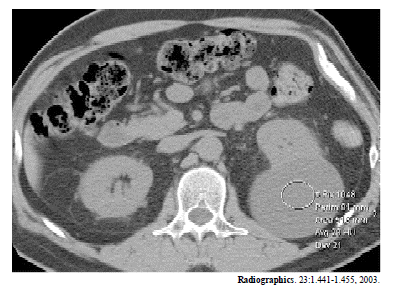

Enunciado 542704-1

A figura acima mostra um corte de tomografia computadorizada de um homem com 47 anos de idade. Considerando essa imagem e as patologias a ela associadas, julgue os seguintes itens.

Quando a tomografia indica suspeição em um nódulo renal, a biópsia percutânea é recomendada.

Enunciado 542703-1

Cistos renais são normalmente assintomáticos.